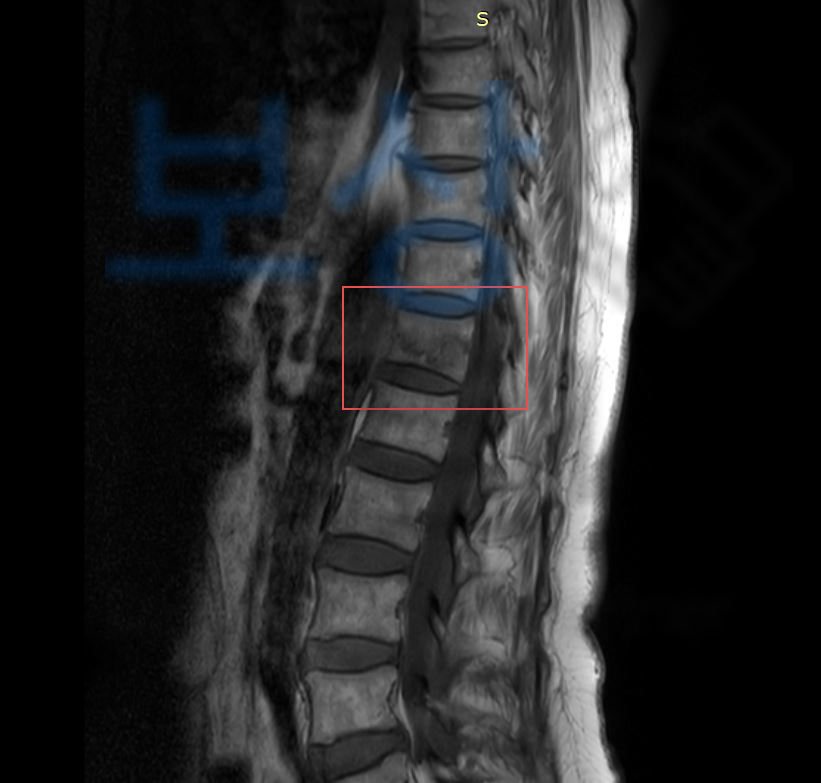

흉추 12번의 압박골절 S22070

진단을 받게 되었습니다.

흉추12번 을 의무기록지를 보면 많이들 T12라고 표기되어있는데요, 등뼈 (Thoracic vertebrae)의 약자로 T12 는 흉추12번 을 가리킵니다. 위 사고로 약물치료와 허리보조기 착용을 해야했던 상황..